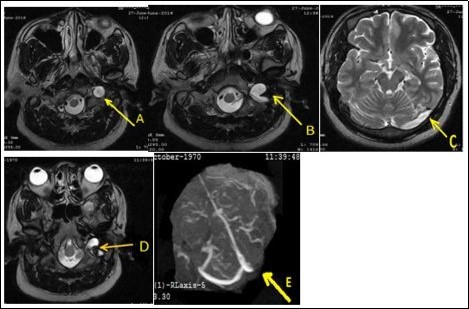

A 46-year-old man was admitted in neurology on June 27, 2016 for left occipito-temporal headache progressively for 2 weeks associated sometimes with nausea and rarely vomiting. He underwent a physical examination of an ophthalmologist and then by a physician of Otorhinolaryngology who had not diagnosed any pathology. On admission, somatic examination was normal. Routine biologic test were normal kidney, hepatic, ionogram, blood count were normal, sedimentation rate was 22 mm /h and C-reactive protein was less normal). The activated cephalin time and the plasmatic homocysteinemia were normal. The activity of protein S and the activated protein C were normal. The chest X-ray and electrocardiogram were normal. The brain ct-scan suspected a left transverse sinus thrombosis. Venous magnetic resonance angiography displayed a left internal jugular vein thrombosis extended to the left transverse sinus associated with a left ethmoidal sinusitis (Figure 1). The cervical doppler was normal. Treatment with low molecular weight heparin was initiated and then replaced with antivitamins K to achieve an international normalized ratio (INR) between 2 and 3 in addition to ofloxacin for 2 weeks and paracetamol. After three months, its remains a partiel jugular thrombosis with persistance of complete transverse sinus thrombosis.

Figure 1.Thrombosis of the left internal jugular vein extended to the transverse sinus (A, B, C). After three months of anticoagulant therapy, it remains a partial thrombosis of the jugular vein (D) and complete thrombosis of the transverse sinus (E).